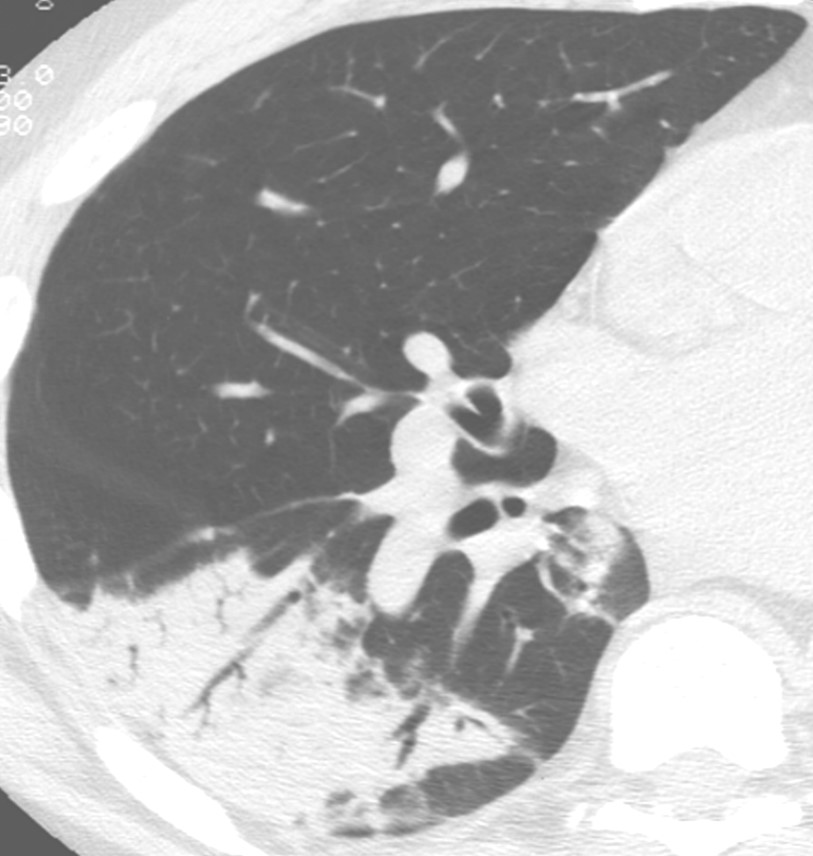

INDETERMINATE FOR UIP

Criteria for a diagnosis of indeterminate for UIP:3,6

- Subpleural and basal predominance

AND - Subtle reticulation, may have ground-glass opacity (mild) or distortion (“early UIP pattern”)

AND - Distribution or features of fibrosis not consistent with specific etiology (“truly indeterminate”)

Example

When characteristics suggestive of fibrosis are visible on HRCT scans but do not meet the criteria of UIP or probable UIP, the images should be classified as indeterminate for UIP.5 UIP pattern may be found on histological testing of patients with HRCT patterns indeterminate for UIP.3,6

Image courtesy of and used with permission from Robert Suh, MD.